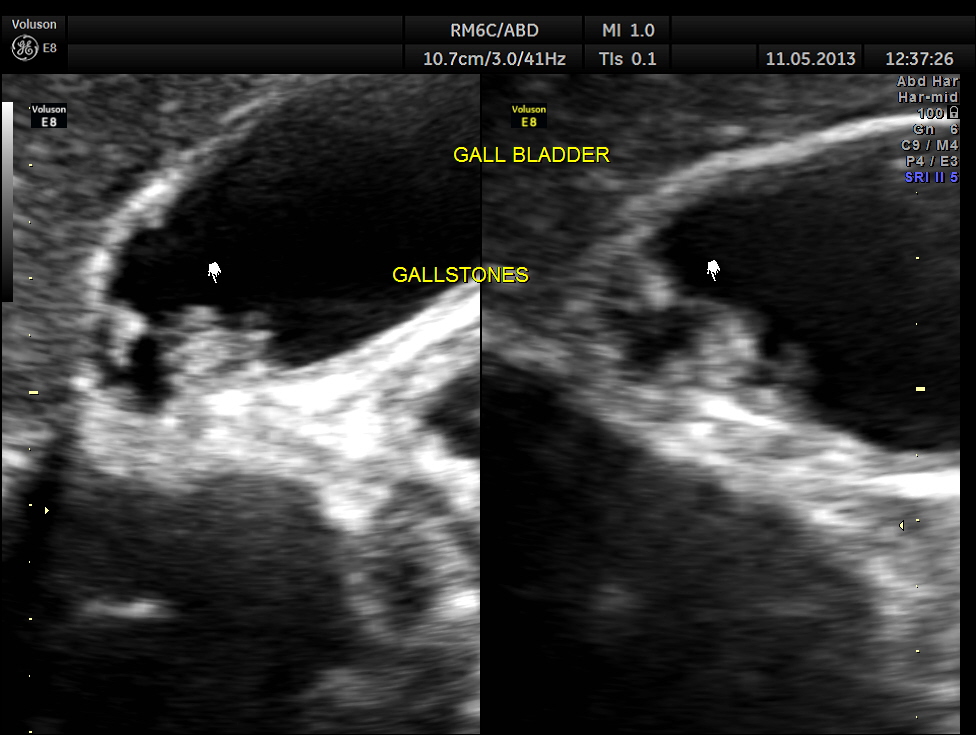

Gall stones were seen .

The diagnosis offered was Cholelithiasis , Choledochal cysts Type IV A and incidental bi cornuate uterus.